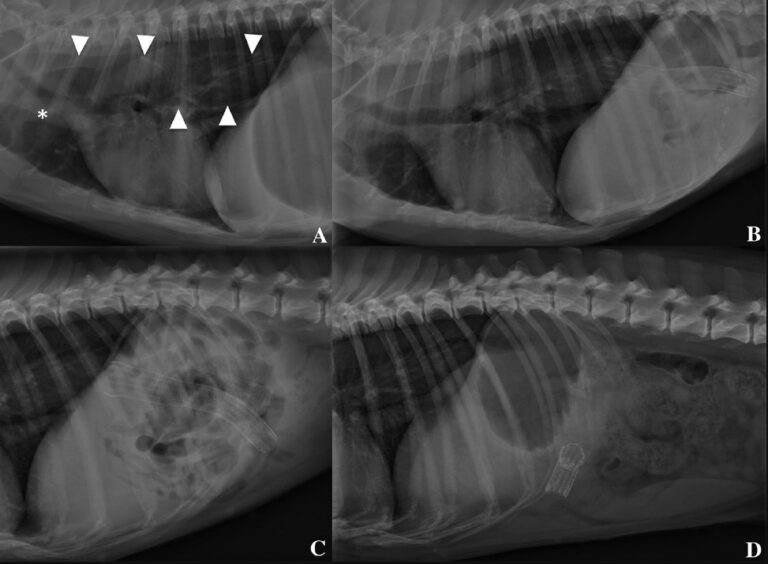

- Röntgenfoto's: Röntgenfoto's van de buik kunnen een vergrote milt laten zien, maar geven geen gedetailleerde informatie over de aard van de tumor.

- Echografie: Echografie is een betere optie voor het beoordelen van de milt. Het kan de grootte en vorm van de tumor laten zien en kan ook helpen bij het opsporen van bloeding in de buikholte.

- CT-scan of MRI: In sommige gevallen kan een CT-scan of MRI nodig zijn om een gedetailleerder beeld te krijgen van de tumor en de omliggende organen. Dit is vooral belangrijk als er sprake is van uitzaaiing.